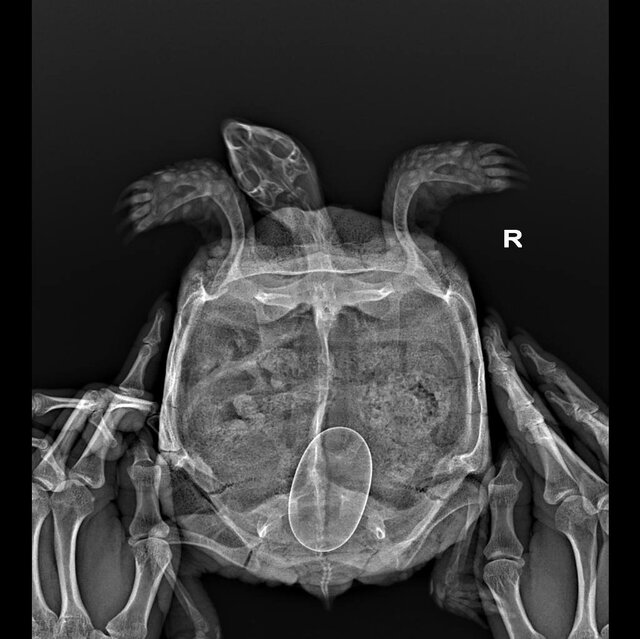

Если кратко, за последние несколько лет мне отдали знакомые люди две черепахи. Я стала за ними ухаживать, любить и растить, купила террариум, лампы, набираю сено на зиму на подстилку, летом гуляют в вольере на улице. В общем оказалось, что они разнополые, когда только появлялась каждая из них я не смогла различить, потому что были похожи. Но когда они стали половозрелые, я подумала может у них что-то получится и это случилось в этом году. На ренгене (30.09.2023) я узнала, что у девочки одно яйцо и она начала проявлять беспокойство, отказывалась от еды и закапывалась в подстилку. В клинике сказали ждать, у них не было такого опыта с беременными сухопутными черепахами. Я начала искать информацию в интернете, смотреть видео и вроде бы всё окей она сама прекрасно справится. Но сегодня 27 октября, я уже с нейросетью искала информацию, очень переживаю и уже готова пойти в ветклинику и последовать совету лопнуть и вытащить яйцо, как это делают попугаям с проблемой откладки. У меня нет в городе больше специалистов в принципе по черепахам. Есть ли тут ветврачи или люди с опытом, что может помочь определить проблему? Или всё нормально и стоит бить тревогу, если она и за ноябрь не отложит яйцо?

Клоака увеличилась за последние пару дней, отверстие будто стало больше и она стала часто тужиться, мне предлагали немного вазелином смазывать, так я заметила, что яйцо ушло глубже, потому что оно было почти у отверстия. Сказали прививки не надо, потому что витамины делали в июле, яйцо очень твердое и кальция нормально в организме. Может у неё яйцо не в правильном положении? Вот прилагаю ренген. Если всё серьезно я поеду в Москву, если вариант, что в ветклинике как попугаю вытащат яйцо - хорошо я так и сделаю. Я купаю раз в неделю в тазике черепаху, оставляю в теплой воде, аппетит хороший и пьет из миски воду сама. Но тужится, и так весь месяц по нарастающей, я боюсь, что это долго

Девочка, среднеазиатская черепаха, больше 10 лет, вес 704гр

врач ответила, что яйцо крупное, но должно быть всё хорошо. Но если будет видно, что яйцо стоит в клоаке и ни туда ни сюда - да, можно как с птицами, вагинальным зеркалом расширить клоаку, асперировать содержимое яйца иглой и пинцетом вытащить скорлупу. Но это должен делать тот, кто понимает что делает.